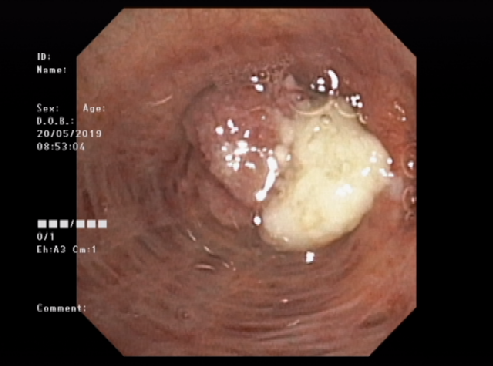

为进一步提高我院呼吸内镜技术服务水平。日前,医院引进了最先进的奥林巴斯OLYMPUS 高清电子支气管镜CV-170,并于5月20日成功为一名73岁患者完成了首例电子支气管镜检查。该患者在支气管镜检查中,通过钳夹还取得活检病理组织样本。

经内一科徐兆平医生介绍,电子支气管镜检查对气道和肺内病变诊断上非常重要。通过电子支气管镜可以更好地观察肺叶、段及亚段气道内病变部位及大小、肿瘤侵及部位等,可在内镜下取到明确的病理样本。对肺部感染、肺部肿瘤、不明原因咳嗽、肺结核、清除气道分泌物等方面能很好的起到辅助诊断和治疗作用。